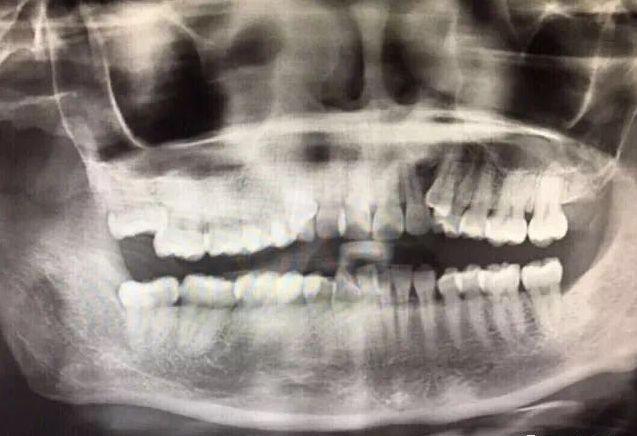

口腔CT檢查,牙齒問題一目了然

矯正前,牙齒不齊,發(fā)灰